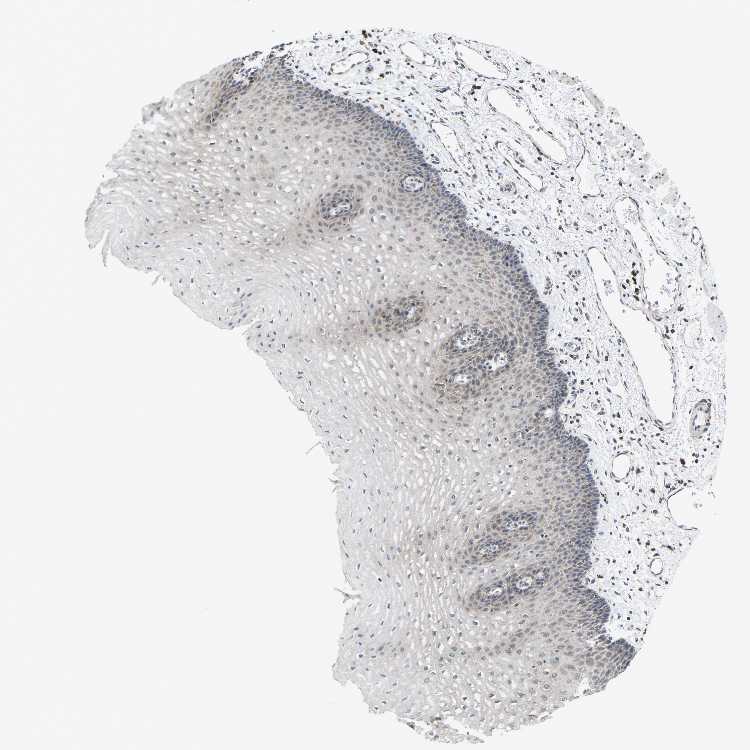

ESOPHAGUS - Antibody stainingi

Antibody staining in the annotated cell types in the current human tissue is reported as not detected, low, medium, or high, based on conventional immunohistochemistry profiling in selected tissues. This score is based on the combination of the staining intensity and fraction of stained cells.

Each image is clickable and will lead to virtual microscopy that enables deeper exploration of all samples and also displays staining intensity scores, fraction scores and subcellular localization as well as patient and tissue information for each sample.

Antibody HPA014907

Squamous epithelial cells Low